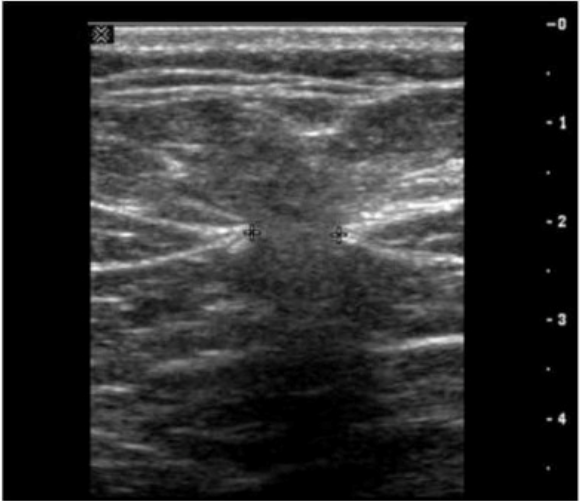

Which condition is demonstrated in this image of the groin?

Answer : D

The ultrasound image demonstrates bowel loops with peristalsis visualized within the inguinal canal, which is diagnostic of an inguinal hernia---more specifically, an indirect inguinal hernia. Indirect hernias pass through the deep inguinal ring and may extend into the scrotum, appearing sonographically as bowel-containing masses adjacent to or within the scrotal sac. Peristaltic motion confirms the presence of viable bowel content.

This finding is typical in indirect inguinal hernias, which are more common in males and often congenital due to a patent processus vaginalis. The herniated bowel can be traced through the inguinal canal, as seen in this image.

Comparison of answer choices:

A . Hematocele presents as a complex fluid collection surrounding the testis, often due to trauma---no complex fluid or trauma is apparent here.

B . Testicular rupture shows discontinuity of the tunica albuginea and irregular testicular contour---none of which is seen.

C . Orchiectomy would show an absent testis---this is not the case here.

D . Indirect hernia is correct. The presence of bowel with peristalsis in the inguinal canal is diagnostic.